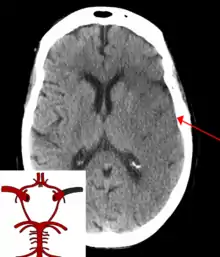

![]() | |

| CT scan of the brain showing a prior right-sided ischemic stroke from blockage of an artery. Changes on a CT may not be visible early on.[1] | |

The biggest risk factor for stroke is high blood pressure.[6] Other risk factors include high blood cholesterol, tobacco smoking, obesity, diabetes mellitus, a previous TIA, end-stage kidney disease, and atrial fibrillation.[2][6][7] An ischemic stroke is typically caused by blockage of a blood vessel, though there are also less common causes.[12][13][14] A hemorrhagic stroke is caused by either bleeding directly into the brain or into the space between the brain's membranes.[12][15] Bleeding may occur due to a ruptured brain aneurysm.[12] Diagnosis is typically based on a physical exam and supported by medical imaging such as a CT scan or MRI scan.[8] A CT scan can rule out bleeding, but may not necessarily rule out ischemia, which early on typically does not show up on a CT scan.[9] Other tests such as an electrocardiogram (ECG) and blood tests are done to determine risk factors and rule out other possible causes.[8] Low blood sugar may cause similar symptoms.[8]

Stroke is diagnosed through several techniques: a neurological examination (such as the NIHSS), CT scans (most often without contrast enhancements) or MRI scans, Doppler ultrasound, and arteriography. The diagnosis of stroke itself is clinical, with assistance from the imaging techniques. Imaging techniques also assist in determining the subtypes and cause of stroke. There is yet no commonly used blood test for the stroke diagnosis itself, though blood tests may be of help in finding out the likely cause of stroke.[67] In deceased people, an autopsy of stroke may help establishing the time between stroke onset and death.

CT scans may not detect an ischemic stroke, especially if it is small, of recent onset,[9] or in the brainstem or cerebellum areas (posterior circulation infarct). MRI is better at detecting a posterior circulation infarct with diffusion-weighted imaging.[70] A CT scan is used more to rule out certain stroke mimics and detect bleeding.[9] The presence of leptomeningeal collateral circulation in the brain is associated with better clinical outcomes after recanalization treatment.[71] Cerebrovascular reserve capacity is another factor that affects stroke outcome – it is the amount of increase in cerebral blood flow after a purposeful stimulation of blood flow by the physician, such as by giving inhaled carbon dioxide or intravenous acetazolamide. The increase in blood flow can be measured by PET scan or transcranial doppler sonography.[72] However, in people with obstruction of the internal carotid artery of one side, the presence of leptomeningeal collateral circulation is associated with reduced cerebral reserve capacity.[73]